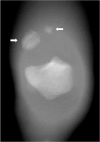

Normal development of the patella typically involves fusion of secondary ossification centers into a single bone during adolescence, with failure of fusion resulting in bipartite and tripartite patellae. In such variants, injury to incomplete ossification center fusion, though uncommon, has been reported to occur in the setting of traumatic quadriceps tendon rupture. The authors present a rare and complex case of traumatic bipartite fragment separation, patellar avulsion, and a complex partial quadriceps tendon tear confirmed surgically in a 36-year-old male. In this case, a tear in the lateral aspect of the quadriceps tendon attached to the nonfused patellar ossification center resulted in retraction of the band containing the bipartite fragment and separation of the patellar fragments, with superior displacement of the smaller bony avulsion likely due to complex attachments from the medial aspect of the quadriceps tendon. Knowledge of the classical locations of a bipartite and tripartite patella can aid in the differentiation of the anatomic variant versus patellar avulsion. Additionally, knowledge of the variable and complex nature of the quadriceps tendon aids in understanding the process of patellar avulsions and various tears, leading to the appropriate orthopedic management.